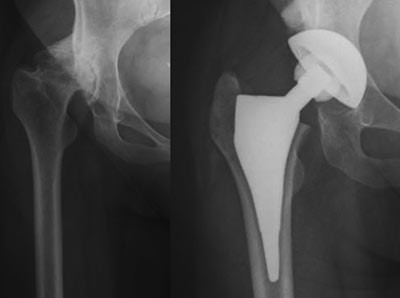

Harris’ hofteskår ble målt preoperativt og postoperativt etter ett år. Gjennomsnittlig skår preoperativt var 49 (spredning 27 – 66) og postoperativt 97 (spredning 76 – 100). Preoperativt var det aktuelle bein kortere (1 – 3 cm) hos 20 pasienter. Postoperativt var beina like lange hos 35 pasienter, hos én pasient var beinet fortsatt 1 cm for kort, og hos én pasient var beinet blitt 1 cm for langt (overkorreksjon). Eksempler på bruk av den individtilpassede hofteprotesen fremgår av figur 6, figur 7 og e-figur 8.